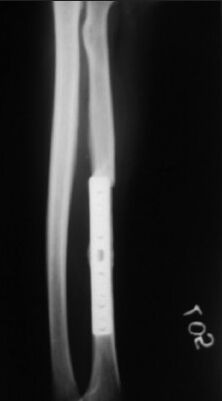

A 38-year-old male presented to our institution for peri-implant fracture of left radius that occurred after two years of radius plating with LC DCP (Synthes, India). The X-ray showed a transverse fracture of the left radius at the proximal end of the plate [Figure 1]. After routine examination and work up, the patient was taken up for surgery.

Figure 1.

Peri-implant fracture at the proximal end of the plate

The tapering drill bit designed for removal of titanium screws by cutting the threads in the shaft of the screw in the reverse drilling direction was not available. We used a locally manufactured stainless steel hollow mill, actually designed to cut the bone around screw during jammed screw removal from the bone. Using it in a high-speed drill, we were able to grate out the titanium metal at the plate hole - screw head interface which facilitated the plate removal. The protruding screw heads from the bone were then easily held by a nose plier and removed by rotatory motion. To prevent contamination of local tissue by metal particles, wet gauge pieces were kept around each side of the plate. The fracture was reduced and fixed with a new 10-hole titanium locking plate, making new holes on each side of peri-implant fracture [Figure 3].

Figure 3.

X-ray after removal of the original implant and application of the new implant